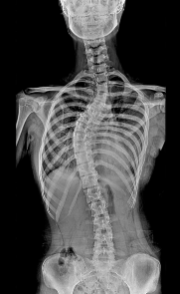

척추측만증은 척추가 정상적인 S자 모양이 아니라 C자나 S자로 휘어진 상태를 말합니다. 척추측만증의 증상은 다음과 같습니다.

척추측만증은 성장기에 더 자주 발생하며, 여성보다 남성에게 더 심하게 나타날 수 있습니다. 척추측만증의 원인은 대부분 알 수 없지만, 유전적 요인이나 근골격계의 이상, 신경계의 이상 등이 관련되어 있을 수 있습니다.